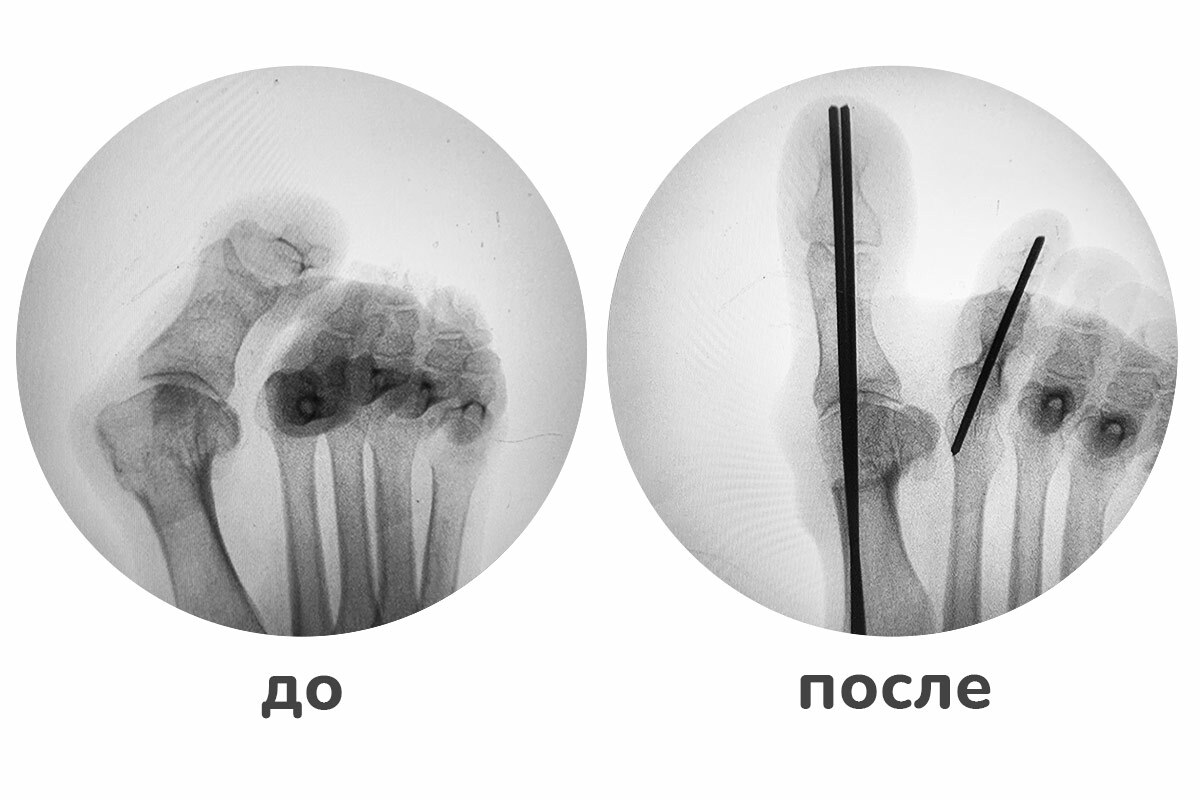

Рентген после операции Hallux valgus